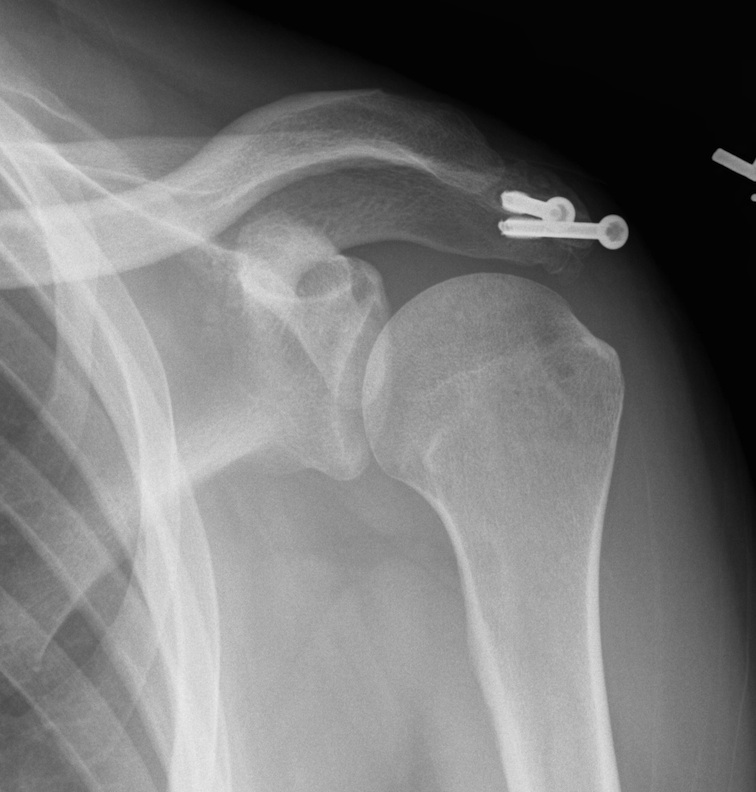

2. ORIF

Indications

Large fragment / mesoacromion

- take down non union

- bone graft / 2 x AP 3.5 mm screws / TBW

- especial care with deltoid reattachment

Outcomes

Atinga et al J Should Elbow 2018

- 32 cases treated with screw fixation and bone graft

- 100% union at 3 months

- 1 infection, 1 seroma, 4 removal of metal work

Risks

Nonunion

- remove screws

- arthroscopic resection

Non union with evidence of lysis around screws